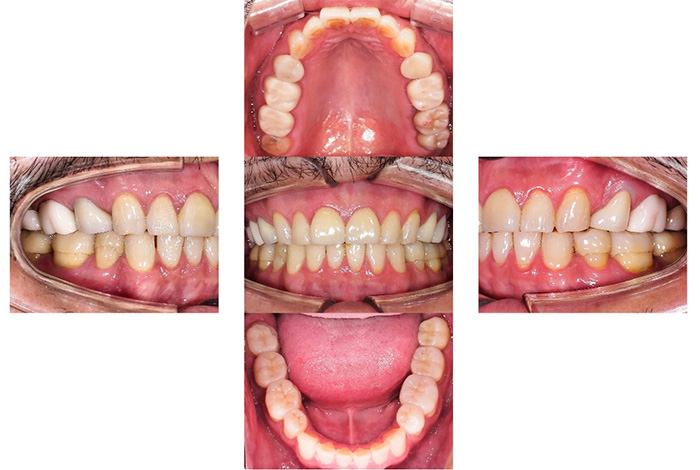

Before

After

前歯の見た目と噛み合わせのバランスを整えたケース

「前歯が強くかみ込んでいる気がする」「歯並びだけでなく、噛み合わせも気になる」

今回の患者様は、ディープバイト(過蓋咬合)による前歯の見た目と噛み合わせを気にされて来院されました。ディープバイトとは、上の前歯が下の前歯に深く重なっている噛み合わせのことで、見た目の問題だけでなく、前歯や顎への負担につながることがあります。

本症例では、マウスピース型矯正装置(インビザライン)を用いて治療を行いました。合計84枚のアライナーを使用し、歯並びだけでなく咬合の深さにも配慮しながら治療を進めました。

治療後は、前歯の見た目のバランスが整い、噛み合わせも改善しました。